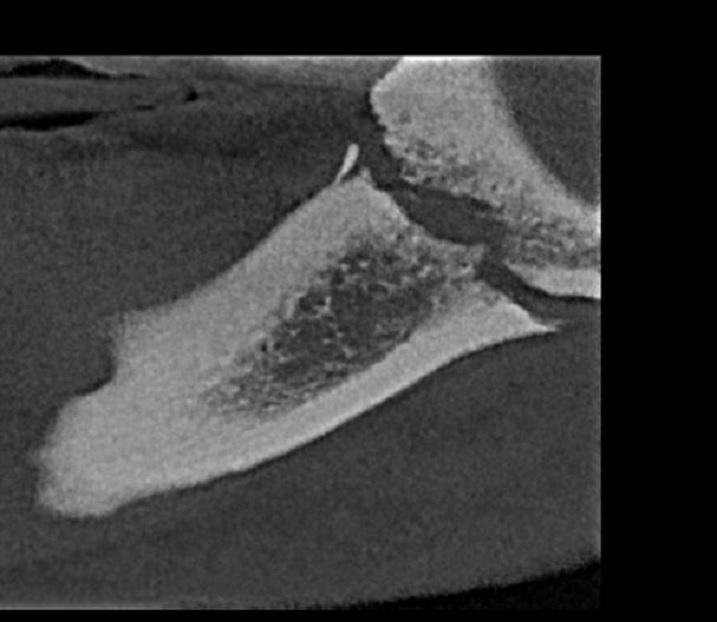

CBCT żuchwy.

Złamanie kości żuchwy po stronie prawej, na granicy gałęzi i trzonu.

Szeroka szczelina - złamanie przebiega w poprzek kości żuchwy w projekcji zęba 48.

Do pilnej interwencji chirurgicznej.